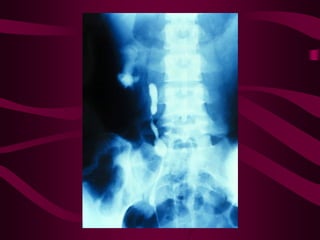

Este documento describe la tuberculosis genitourinaria. Afecta más a hombres que a mujeres. Se transmite principalmente a través de la infección pulmonar primaria y luego se disemina a través de la sangre a los riñones u otros órganos. Causa lesiones como granulomas y necrosis si no se controla, lo que puede provocar complicaciones como abscesos e insuficiencia renal. Se diagnostica mediante pruebas de orina y tratamiento con medicamentos durante varios meses.